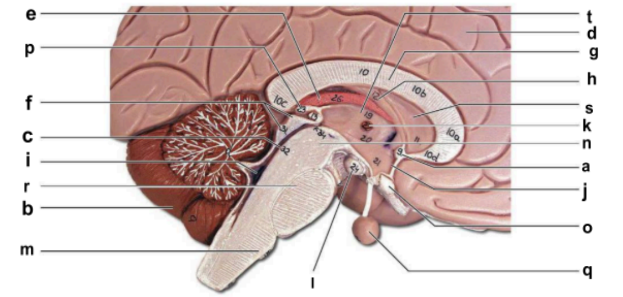

Identify the structure labeled “a” in the image.

anterior commissure

Identify the structure labeled “b” in the image.

cerebellum

Identify the structure labeled “c” in the image.

cerebral aqueduct

Identify the structure labeled “d” in the image.

cerebral hemisphere

Identify the structure labeled “e” in the image.

choroid plexus

Identify the structure labeled “f” in the image.

corpora quadrigemina

Identify the structure labeled “g” in the image.

corpos callosum

Identify the structure labeled “h” in the image.

fornix

Identify the structure labeled “i” in the image.

fourth ventricle

Identify the structure labeled “j” in the image.

hypothalamus

Identify the structure labeled “k” in the image.

interthalamic adhesion

Identify the structure labeled “l” in the image.

mammilary body

Identify the structure labeled “m” in the image.

medulla oblongata

Identify the structure labeled “n” in the image.

midbrain

Identify the structure labeled “o” in the image.

optic chiasma

Identify the structure labeled “p” in the image.

pineal gland

Identify the structure labeled “q” in the image.

pituitary gland

Identify the structure labeled “r” in the image.

pons

Identify the structure labeled “s” in the image.

septum pellucidum

Identify the structure labeled “t” in the image.

thalamus